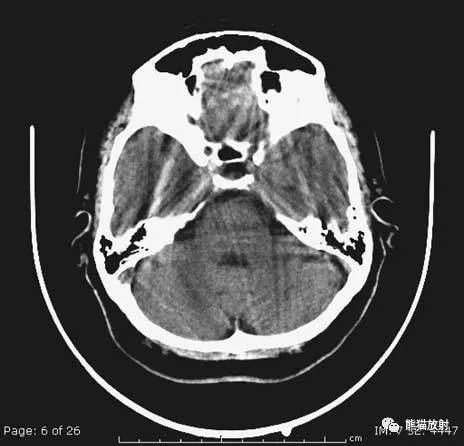

颅脑CT常用的三个窗(图A-C):

- 图A:骨窗(the bone window)

- 图B:脑窗(the brain window)

- 图C:血窗(the blood window)

图A:骨窗;主要用于明确骨折、窦腔病变、颅内积气。

图B:脑窗;可清晰显示灰白质,可发现中风的早期征象或其他导致脑水肿等表现的病变。

图C:血窗;更利于显示硬膜下或颅内出血。

本例表现:骨窗示:右顶骨骨折;三个窗均示:软组织水肿并皮下积气;血窗:少量硬膜下血肿。